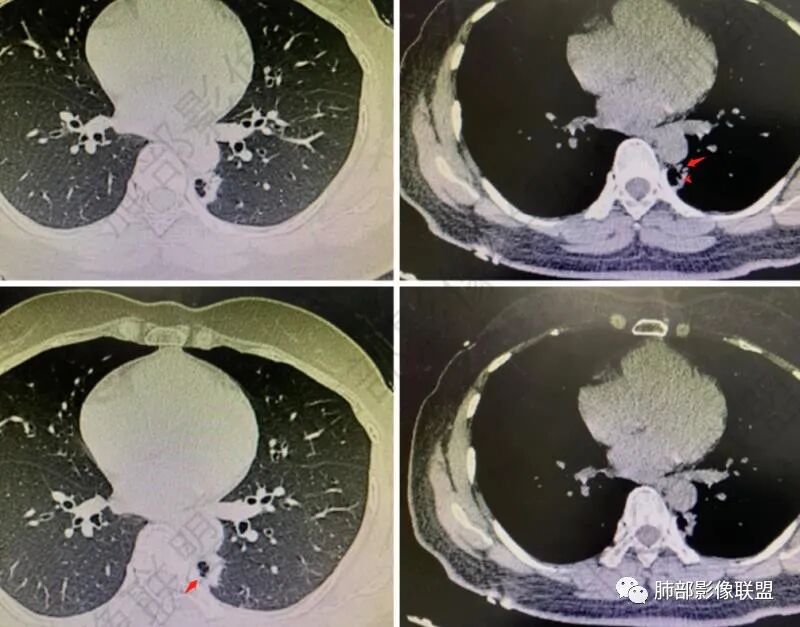

一般多发病灶,我们第一反应:能否一元论?如果不能:就分开分析。

PGGN,小、密度低,边界清,支持原位癌。

这个需要连续的图观察,是否病灶,有待确定

囊腔应该是,周围是否有GGO?还是薄壁?

左下叶脊椎旁:囊实性

1、右肺上叶混合密度磨玻璃结节特征性较强,尤其是后段病灶,边界清楚,应高度警惕微浸润腺癌,这个不用纠结,我们可以等,定期复查行之有效。

左肺下叶背段脊柱旁病灶相当不规则,形态既不符合空洞,也未能围成一完整的囊圈影,未见典型的分叶、毛刺及清楚的磨玻璃晕,前方出入支气管轻度扩张,纵隔窗病灶密度偏高不均,临近胸壁未见侵入。双肺门及纵隔未见增大淋巴结。

客观评价,该病灶缺乏恶性肿瘤影像学特征,尽管我们不能排除恶性。